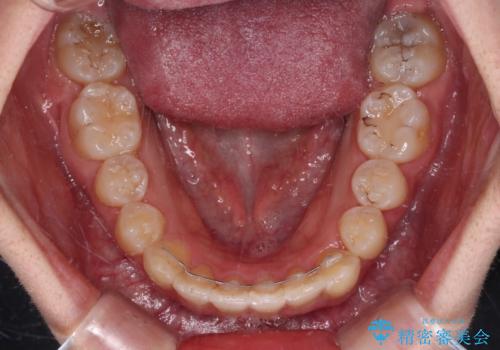

インビザラインでの治療を希望されていましたが、前歯のクロスバイトや下顎小臼歯の捻転が認められたため、インビザライン単独で治療を行うよりも、ワイヤー装置を併用した方が、治療期間の短縮やトラブル回避できると判断し、ワイヤー装置を併用することとしました。

まずはワイヤー装置により前歯のクロスバイトと下顎小臼歯の捻転を改善し、その後インビザラインにより全体を整える矯正治療を行うこととしました。

前歯のクロスバイトは、インビザラインでの改善中に前歯に過剰な力がかかり、歯髄壊死や歯肉退縮を引き起こすことがあります。また下顎小臼歯は寸胴型のため、捻転を排除することが難しいことが知られています。

それをワイヤー装置にて速やかに改善することで、トータルでの治療期間を短くすることができます。